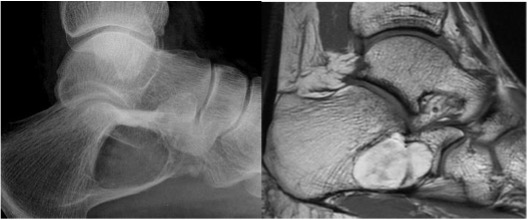

Intraosseous lipoma calcaneum

Intraosseous lipoma

- Typically occurs in the calcaneum

- Well-defined lucent lesion; may contain central calcification

- MRI diagnostic to confirm fatty matrix, seen as high T1 and T2 signal which supresses with fat saturation